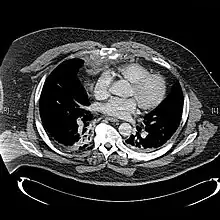

X-rays of the chest are taken in people with chest trauma and symptoms of sternal fractures, and these may be followed by CT scanning.[13] Since X-rays taken from the front may miss the injury, they are taken from the side as well.[14]